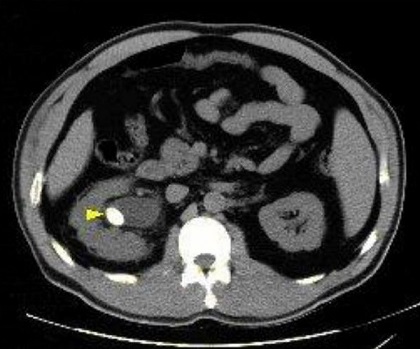

تشخیص دقیق اندازه سنگ، اولین قدم برای سنگ شکنی سنگ لگنچه کلیه است. بر اساس استانداردهای پزشکی، روش های درمانی به سه دسته کلی تقسیم می شوند:

۱. سنگ های لگنچه کوچک تر از ۵ میلی متر

بیش از ۹۰ درصد این سنگ ها با مصرف مایعات زیاد و فعالیت بدنی دفع می شوند. اما اگر به دلیل تنگی مجاری، سنگ دفع نشود، سنگ شکنی برون اندامی (ESWL) بهترین گزینه است.

۲. سنگ های ۵ تا ۲۰ میلی متر لگنچه کلیه

این سنگ ها به دلیل ابعادی که دارند، نمی توانند از لوله حالب عبور کنند. سنگ شکنی در مشهد توسط دکتر فرهادی با دستگاه های پیشرفته انجام می شود تا این سنگ ها به ذرات کوچک تبدیل شده و به راحتی دفع گردند.

۳. سنگ های لگنچه بزرگ تر از ۲۰ میلی متر (سنگ های غول آسا)

بسیاری از مراکز درمانی، درمان سنگ های بزرگ تر از ۲۰ میلی متر را به روش های تهاجمی ارجاع می دهند. اما در مرکز سنگ شکنی دکتر اصغر فرهادی، ما تجربه موفقی در درمان سنگ های تا 55 میلی متر و حتی بزرگ تر (سابقه درمان سنگ ۹۶ میلی متری) را با روش سنگ شکنی بدون جراحی داریم.